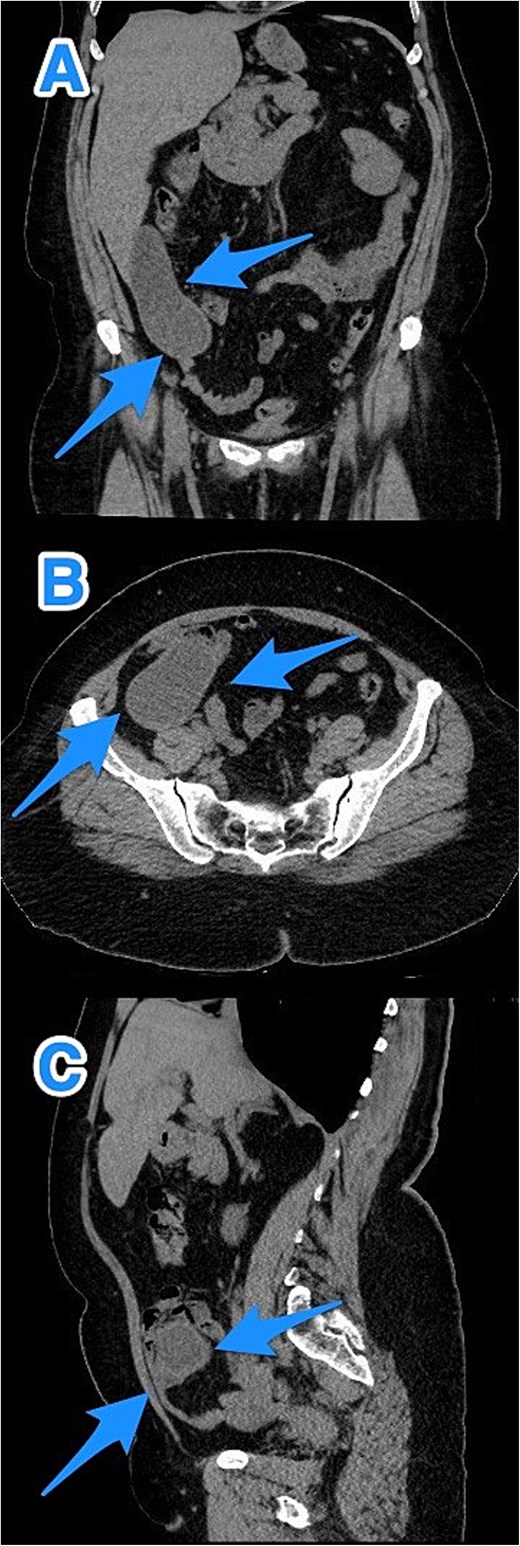

A 46-year-old male with a history of leukemia treated with chemotherapy and primary infertility presented with right lower quadrant abdominal pain of less than one day's duration. He reported associated nausea but no vomiting, changes in bowel habits, or fever. On systemic evaluation, the patient demonstrated stable vital signs, full consciousness, and alertness, with no evidence of severe pain. Abdominal examination revealed rebound tenderness in the RLQ, but the abdomen was otherwise soft, with no tenderness upon palpation of other regions. Laboratory investigations were within normal limits. Abdominal CT with contrast revealed evidence of appendiceal perforation. The liver showed moderate to severe steatosis, but no other remarkable abnormalities were detected (Fig. 5). Due to the perforation near the base of the appendix, a right hemicolectomy was performed. Histopathological examination of the appendix confirmed the diagnosis of LAMN (Fig. 6). The tumor extended to the visceral peritoneum through the perforation site, but there was no evidence of lymphatic, vascular, or perineural invasion. Four reactive lymph nodes were negative for tumor infiltration, and the pathologic TNM staging was pT4, pN0. The specimen also contained acellular mucin evacuated during the surgery. Postoperative recovery was uneventful, and the patient was later transferred to a higher center for comprehensive assessment and continued care.

CT abdomen and pelvis with contrast: (A) coronal, (B) axial, and (C) sagittal views reveal an appendix measuring 22 cm in the right iliac fossa, with edematous wall thickening, minimal surrounding fat stranding, and an adjacent fluid collection measuring 3.3 × 1.8 × 8.5 cm, consistent with a perforated appendix (arrows).